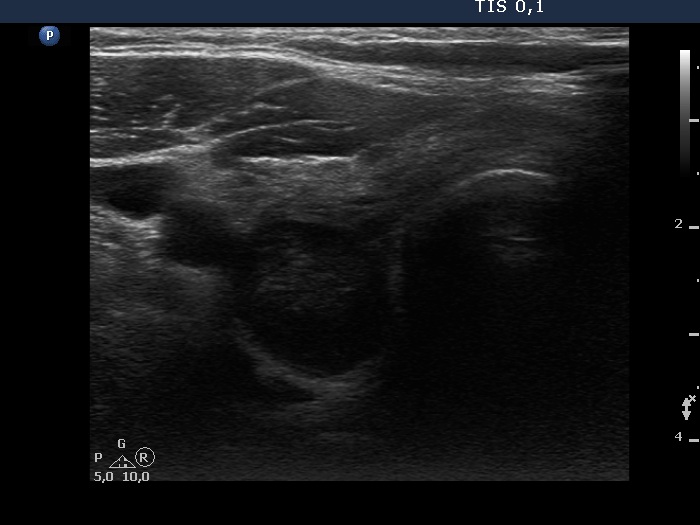

First examination (1st row of images)

Clinical presentation. A 45-year-old man was referred for cytology of a discrete lesion found on ultrasound examination. The patient had been treated for hypothyroidism for several years.

Palpation: no abnormality.

Hormonal evaluation: TSH 2.19 mIU/L on daily100 microgram levothyroxine.

Ultrasonography. The thyroid presented the typical focal form of lymphocytic thyroiditis, it had numerous, tiny, hypoechoic areas. There was a more regularly shaped and larger lesion in the dorsal part of the right lobe. This lesion had at least one punctate echogenic focus.

Aspiration cytology of the lesion resulted in Hashimoto's thyroiditis.